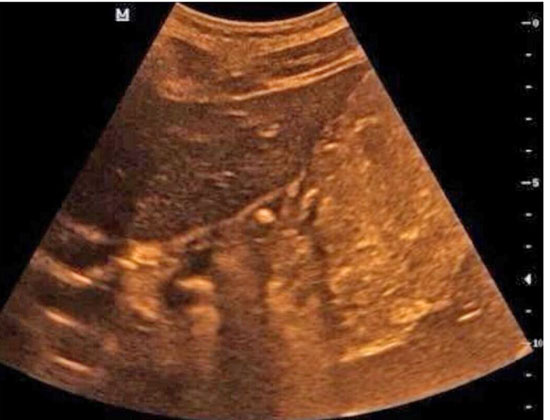

就在这时,有朋友给小英的妈妈推荐了胃肠超声检查。按照约定的时间,小英一大早就空腹来到齐鲁医院青岛院区健康管理中心,喝下了医生为她特制的“黑芝麻糊”后,B超室医生为她进行了胃肠超声检查,结果发现小英胃的贲门口位置有一个大约5mm的溃疡,与她疼痛的位置相符。

胃肠超声,又叫胃十二指肠口服超声造影,是胃肠道疾病的影像学检查方法之一。健康管理中心副主任张萍介绍说,之前超声不能看胃,因为胃是空腔脏器,里面有气体,而超声比较怕气体。但是如果有什么办法可以将胃里的空气赶走,让它变得像实质脏器,问题不就解决了吗?于是胃窗造影剂应运而生。

“胃肠超声就是通过口服纯粮食造影剂,在超声下能够看到粘膜层及胃壁各层结构,筛查疾病,发现可疑病变,并视察病变的范围及侵犯程度。”她说。